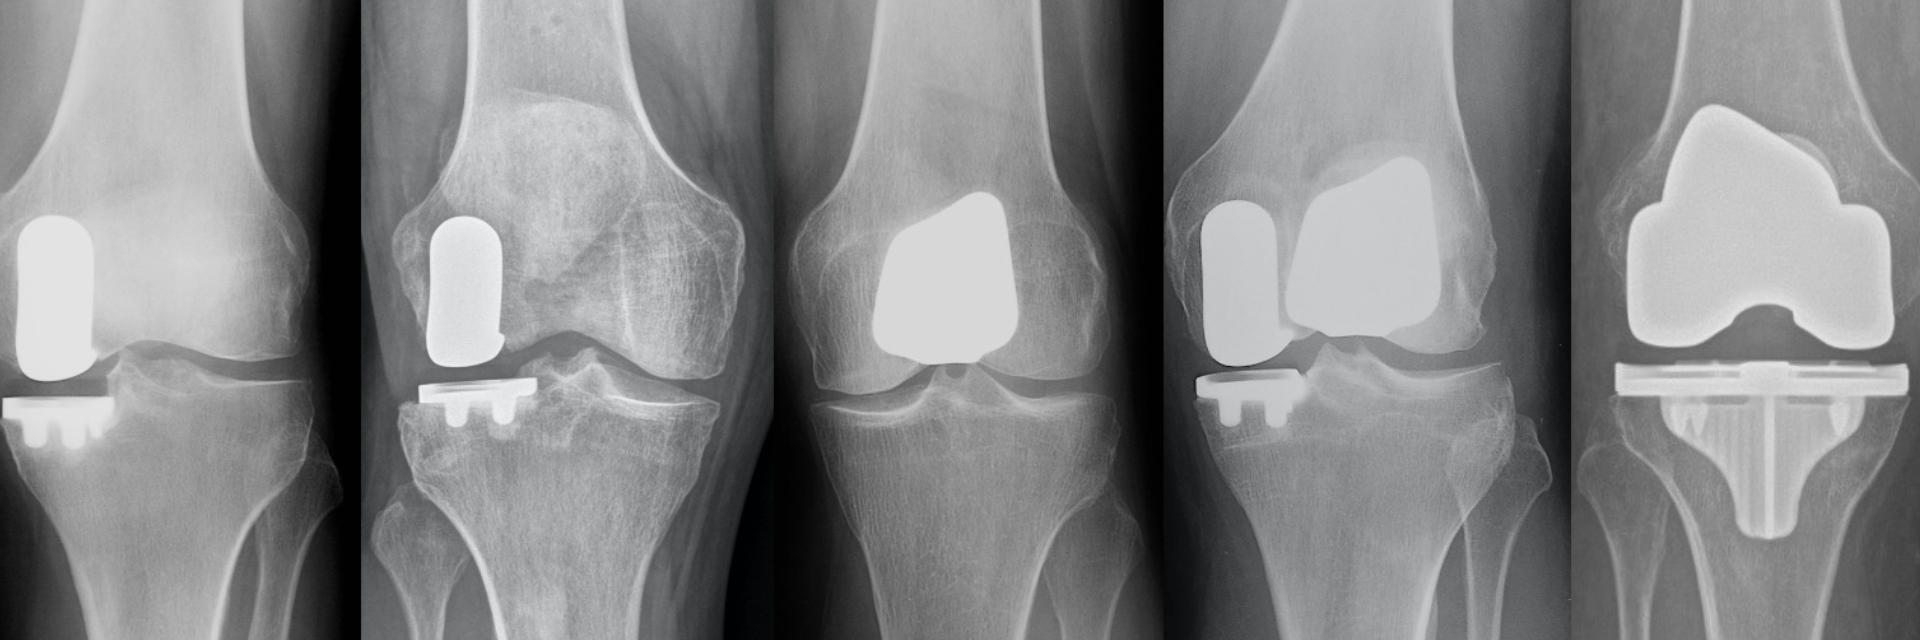

The knee joint is the location where the end of the thigh bone and the top of the shin bone and fibula meet. All of the structures in this location make up the knee joint. The knee joint moves smoothly in healthy knees because of the coating on the end of the bones called cartilage. The Knee joint has three main compartments.

- The Medial Compartment is the inner side of the knee joint between the thigh bone (femur) and shin bone (tibia). Medial compartment is the most common compartment that wears down in the knee and the most common location for partial knee replacement. Partial knee candidates have pain with weight-bearing in just the medial compartment.

- The Lateral Compartment is on the outer side of the knee joint between the thigh bone (femur) and shin bone (tibia). The lateral compartment is the second most common compartment that wears down in the knee. Lateral compartment partial knee candidates have pain with weight-bearing in just the lateral compartment.

- The Patellofemoral Compartment is the third compartment of the knee. This is the compartment in the front of the knee between the kneecap (patella) and the thigh bone (femur). The patella moves down the middle of the two knuckles (condyles) on the end of the femur and increases the efficiency of the quadriceps muscle. Patients with pain in the patellofemoral compartment often describe pain with rising and sitting, stair climbing and knee bending. Patellofemoral partial knee candidates have pain in the anterior compartment under the kneecap (the front of the knee), but no pain in the medial or lateral joint compartments.